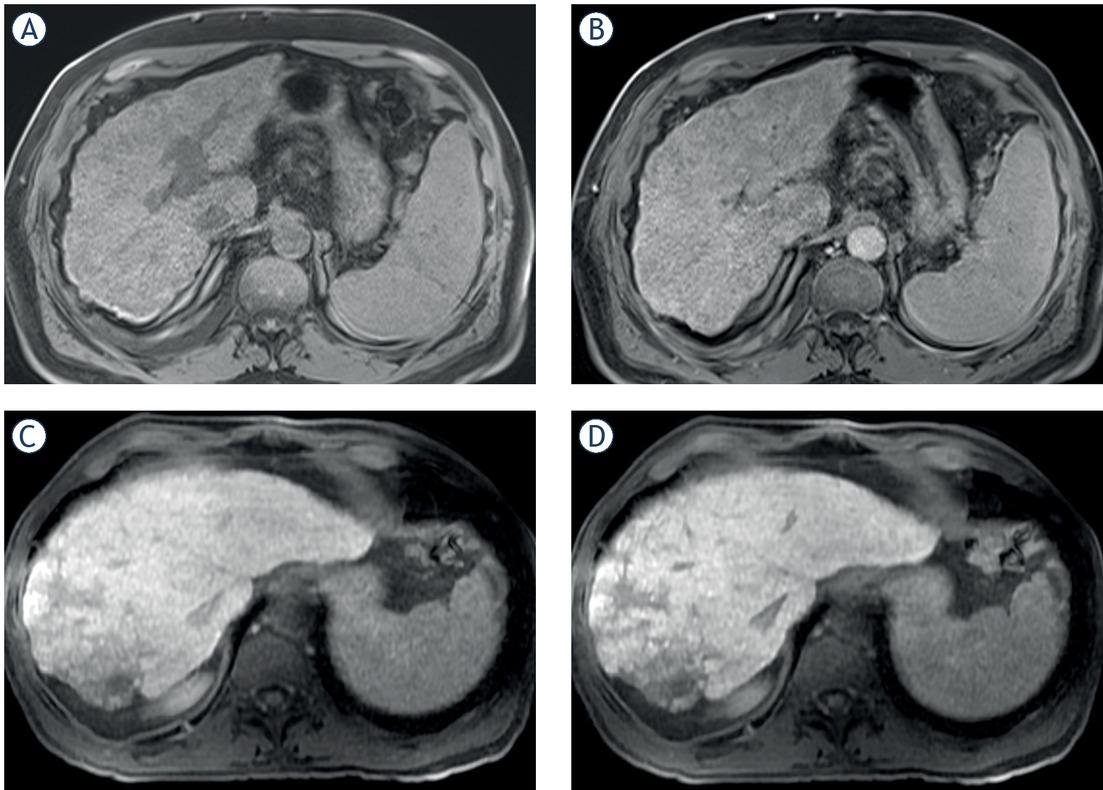

All 10 and 20 minutes HBPs were reviewed by two independent radiologists (A.D. and J.R). The quality of the HBP was classified as 1) adequate, when the liver parenchyma showed signal intensity (SI), higher than the SI of the intrahepatic vessels, or 2) Non-adequate quality, when the SI in the liver parenchyma was non-superior to the SI in intrahepatic vessels (Figure 1).24 Also, the biliary contrast excretion was evaluated qualitatively according to the extension (intrahepatic only and extrahepatic). Inadequate hepatobiliary contrast excretion was defined as the lack of contrast agent in the extra-hepatic bile ducts in the hepatobiliary phase at 20 minutes

Non-adequate quality in the liver uptake of Gadolinium-ethoxybenzyl-diethylenetriamine penta-acetic acid (Gd-EOB-DTPA) in the 20 minutes hepatobiliary phase. (A) and (B): patient with liver cirrhosis Child-Pugh B and clinically significant portal hypertension. (A): Baseline T1w-3D VIBE sequence. (B): the liver showed poor or non-apparent contrast uptake compared to the liver before contrast injection. (C) and (D): patient with liver cirrhosis Child-Pugh A 5 points with no clinically significant portal hypertension. (C): Baseline T1w-3D VIBE sequence. (D): the liver parenchyma showed very heterogeneous uptake of the contrast media, especially in the periphery of the right hepatic lobe.